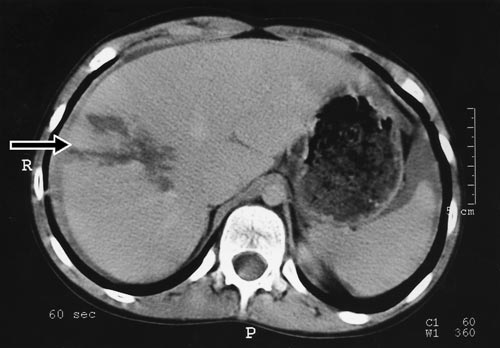

On examination, he was pale with a pulse of 130/minute and blood pressure of 100/60 mmHg. His abdomen was tender in the right upper quadrant with guarding. A CT scan of the abdomen revealed a large laceration to the right lobe of his liver, with a significant amount of free intraperitoneal fluid (Box 2).